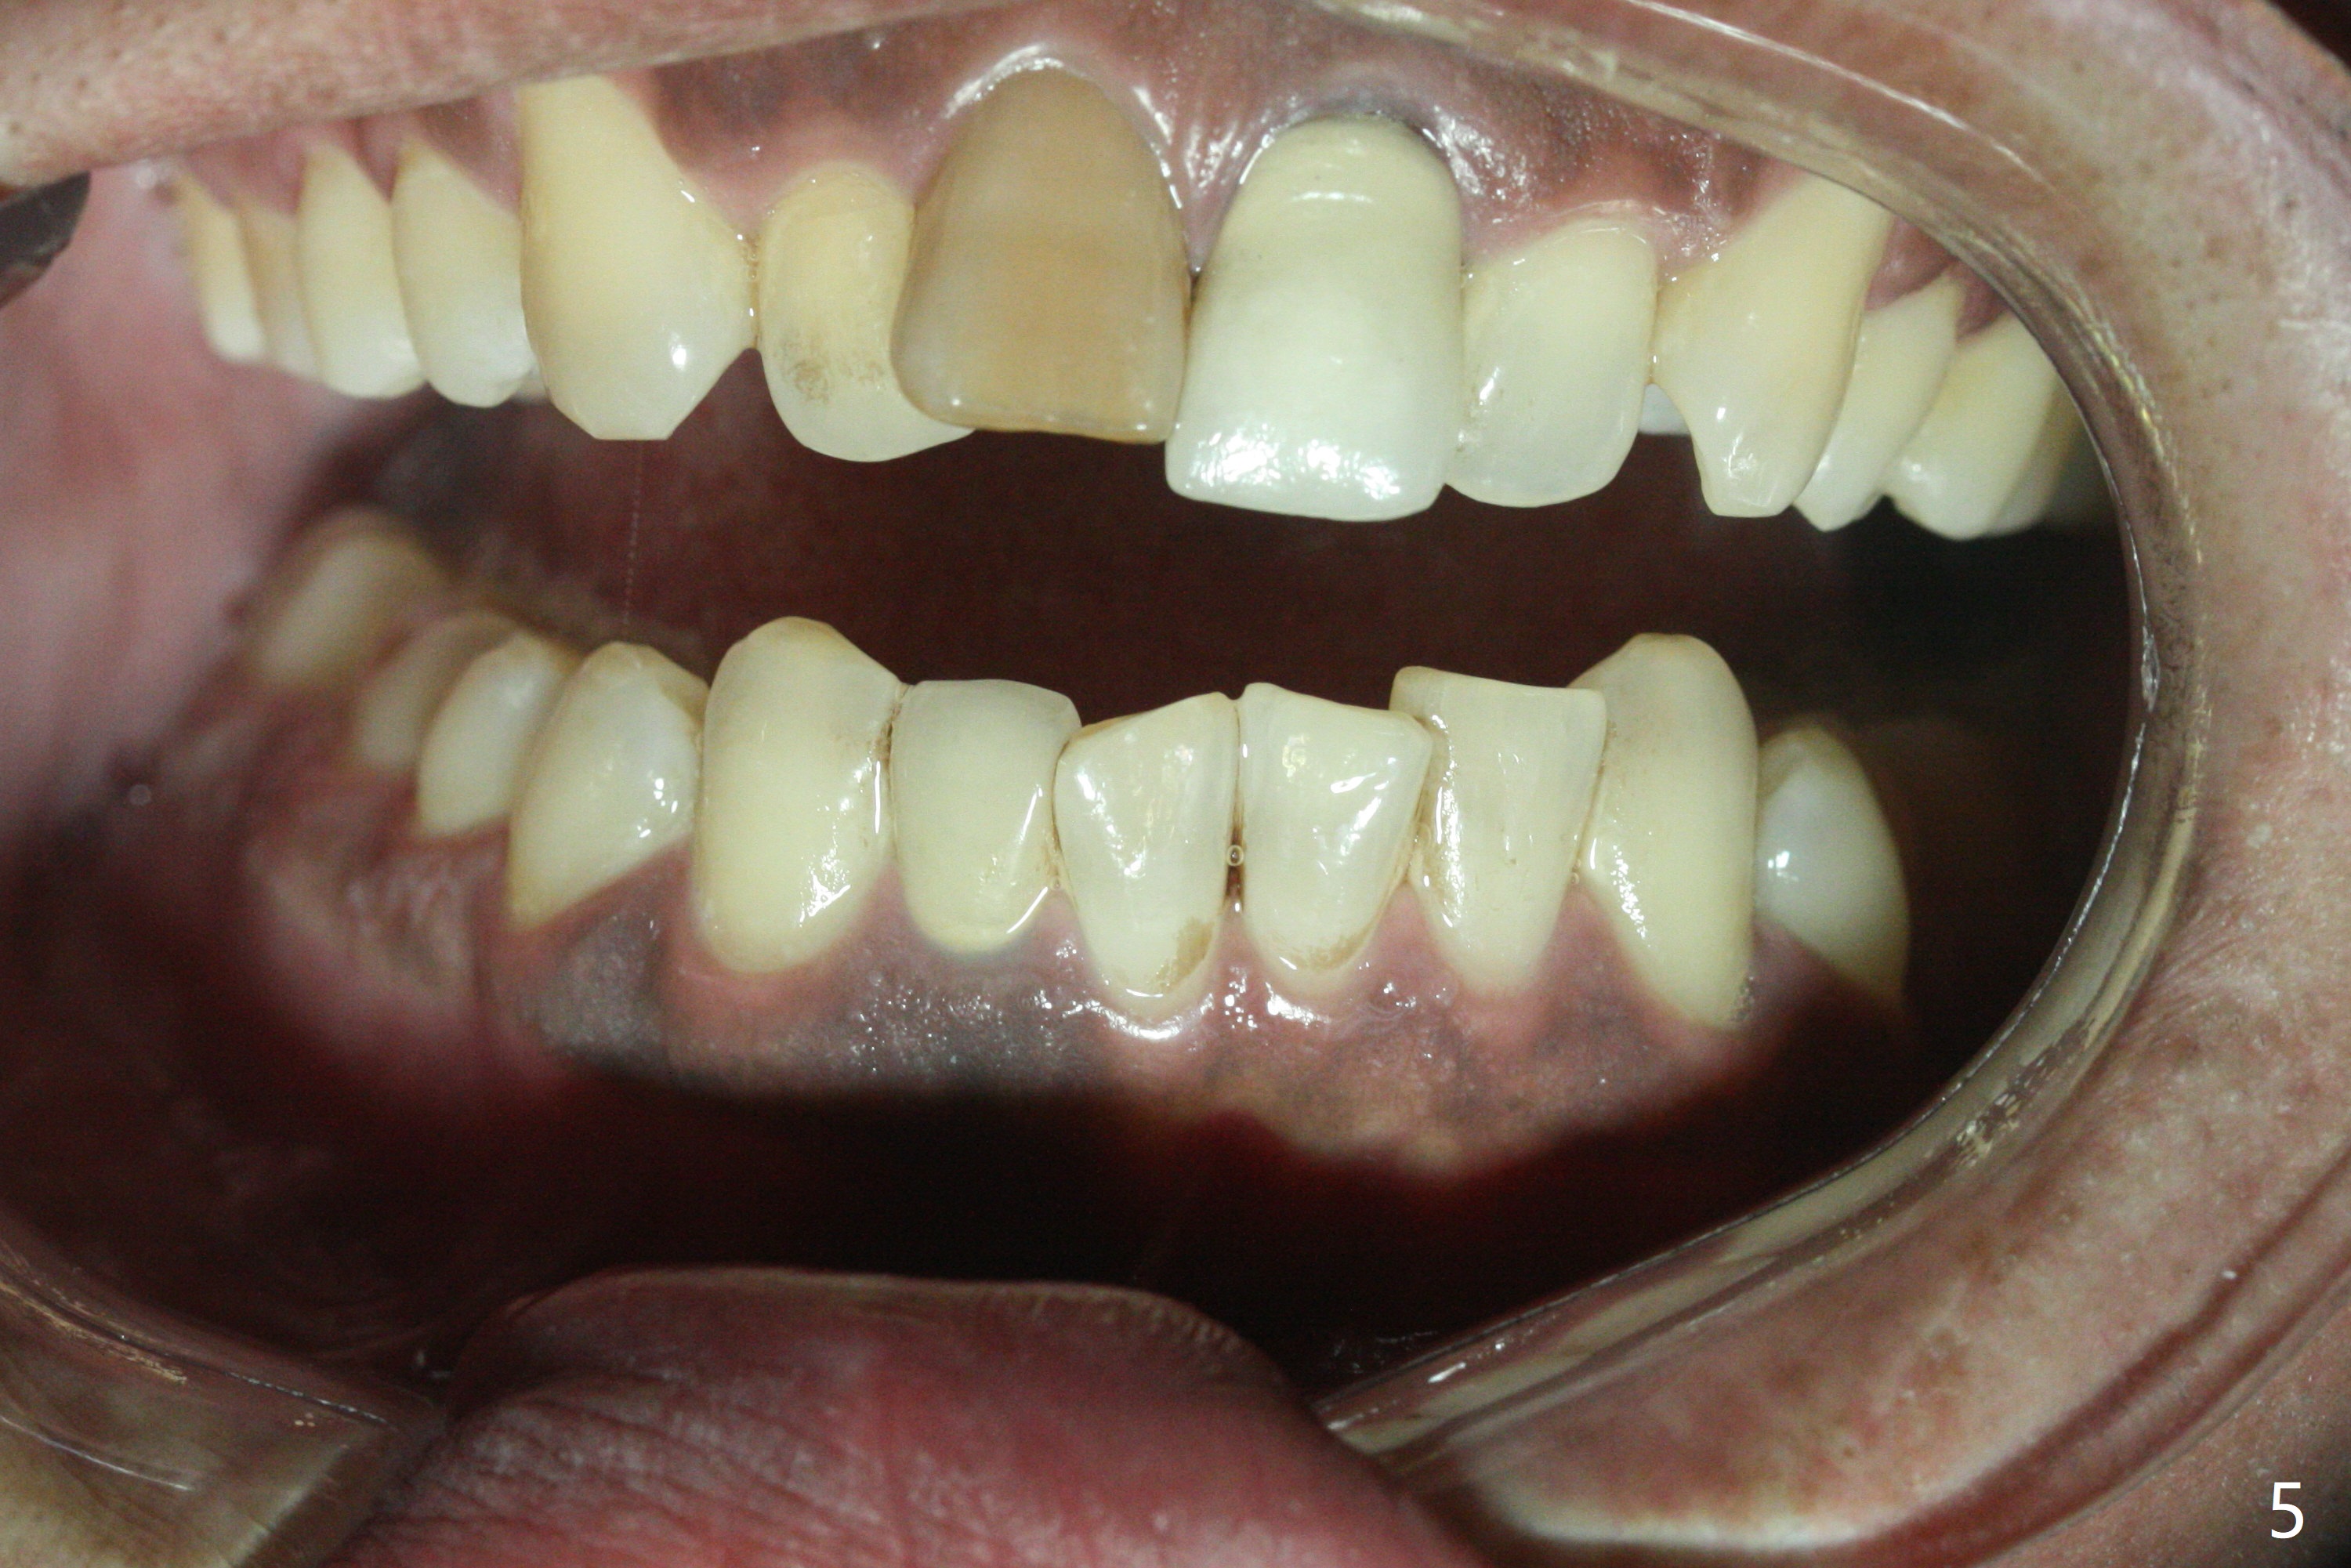

Class II半个牙。这个不用拔牙,Molar distalizaton 和expansion 就可以解决。Oral scan and submit it to Unismile. 建模后。我来帮您设计。张。两个中切牙,位置可以不用排得太完美。排到半程的位置,然后用重做的牙冠来调齐。这样,能减少一些复发的势能。Harry Hu